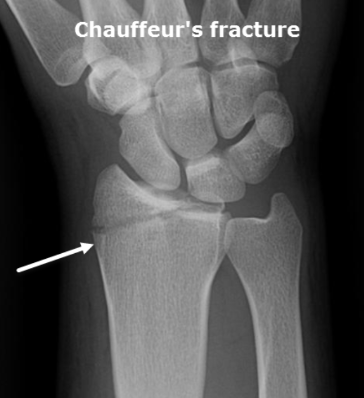

What fracture is this?

Hutchinson (Chauffeur)

What is a Hutchinson (Chauffer) fracture?

Special

Fx of radial styloid process (blow to lateral side of distal forearm)